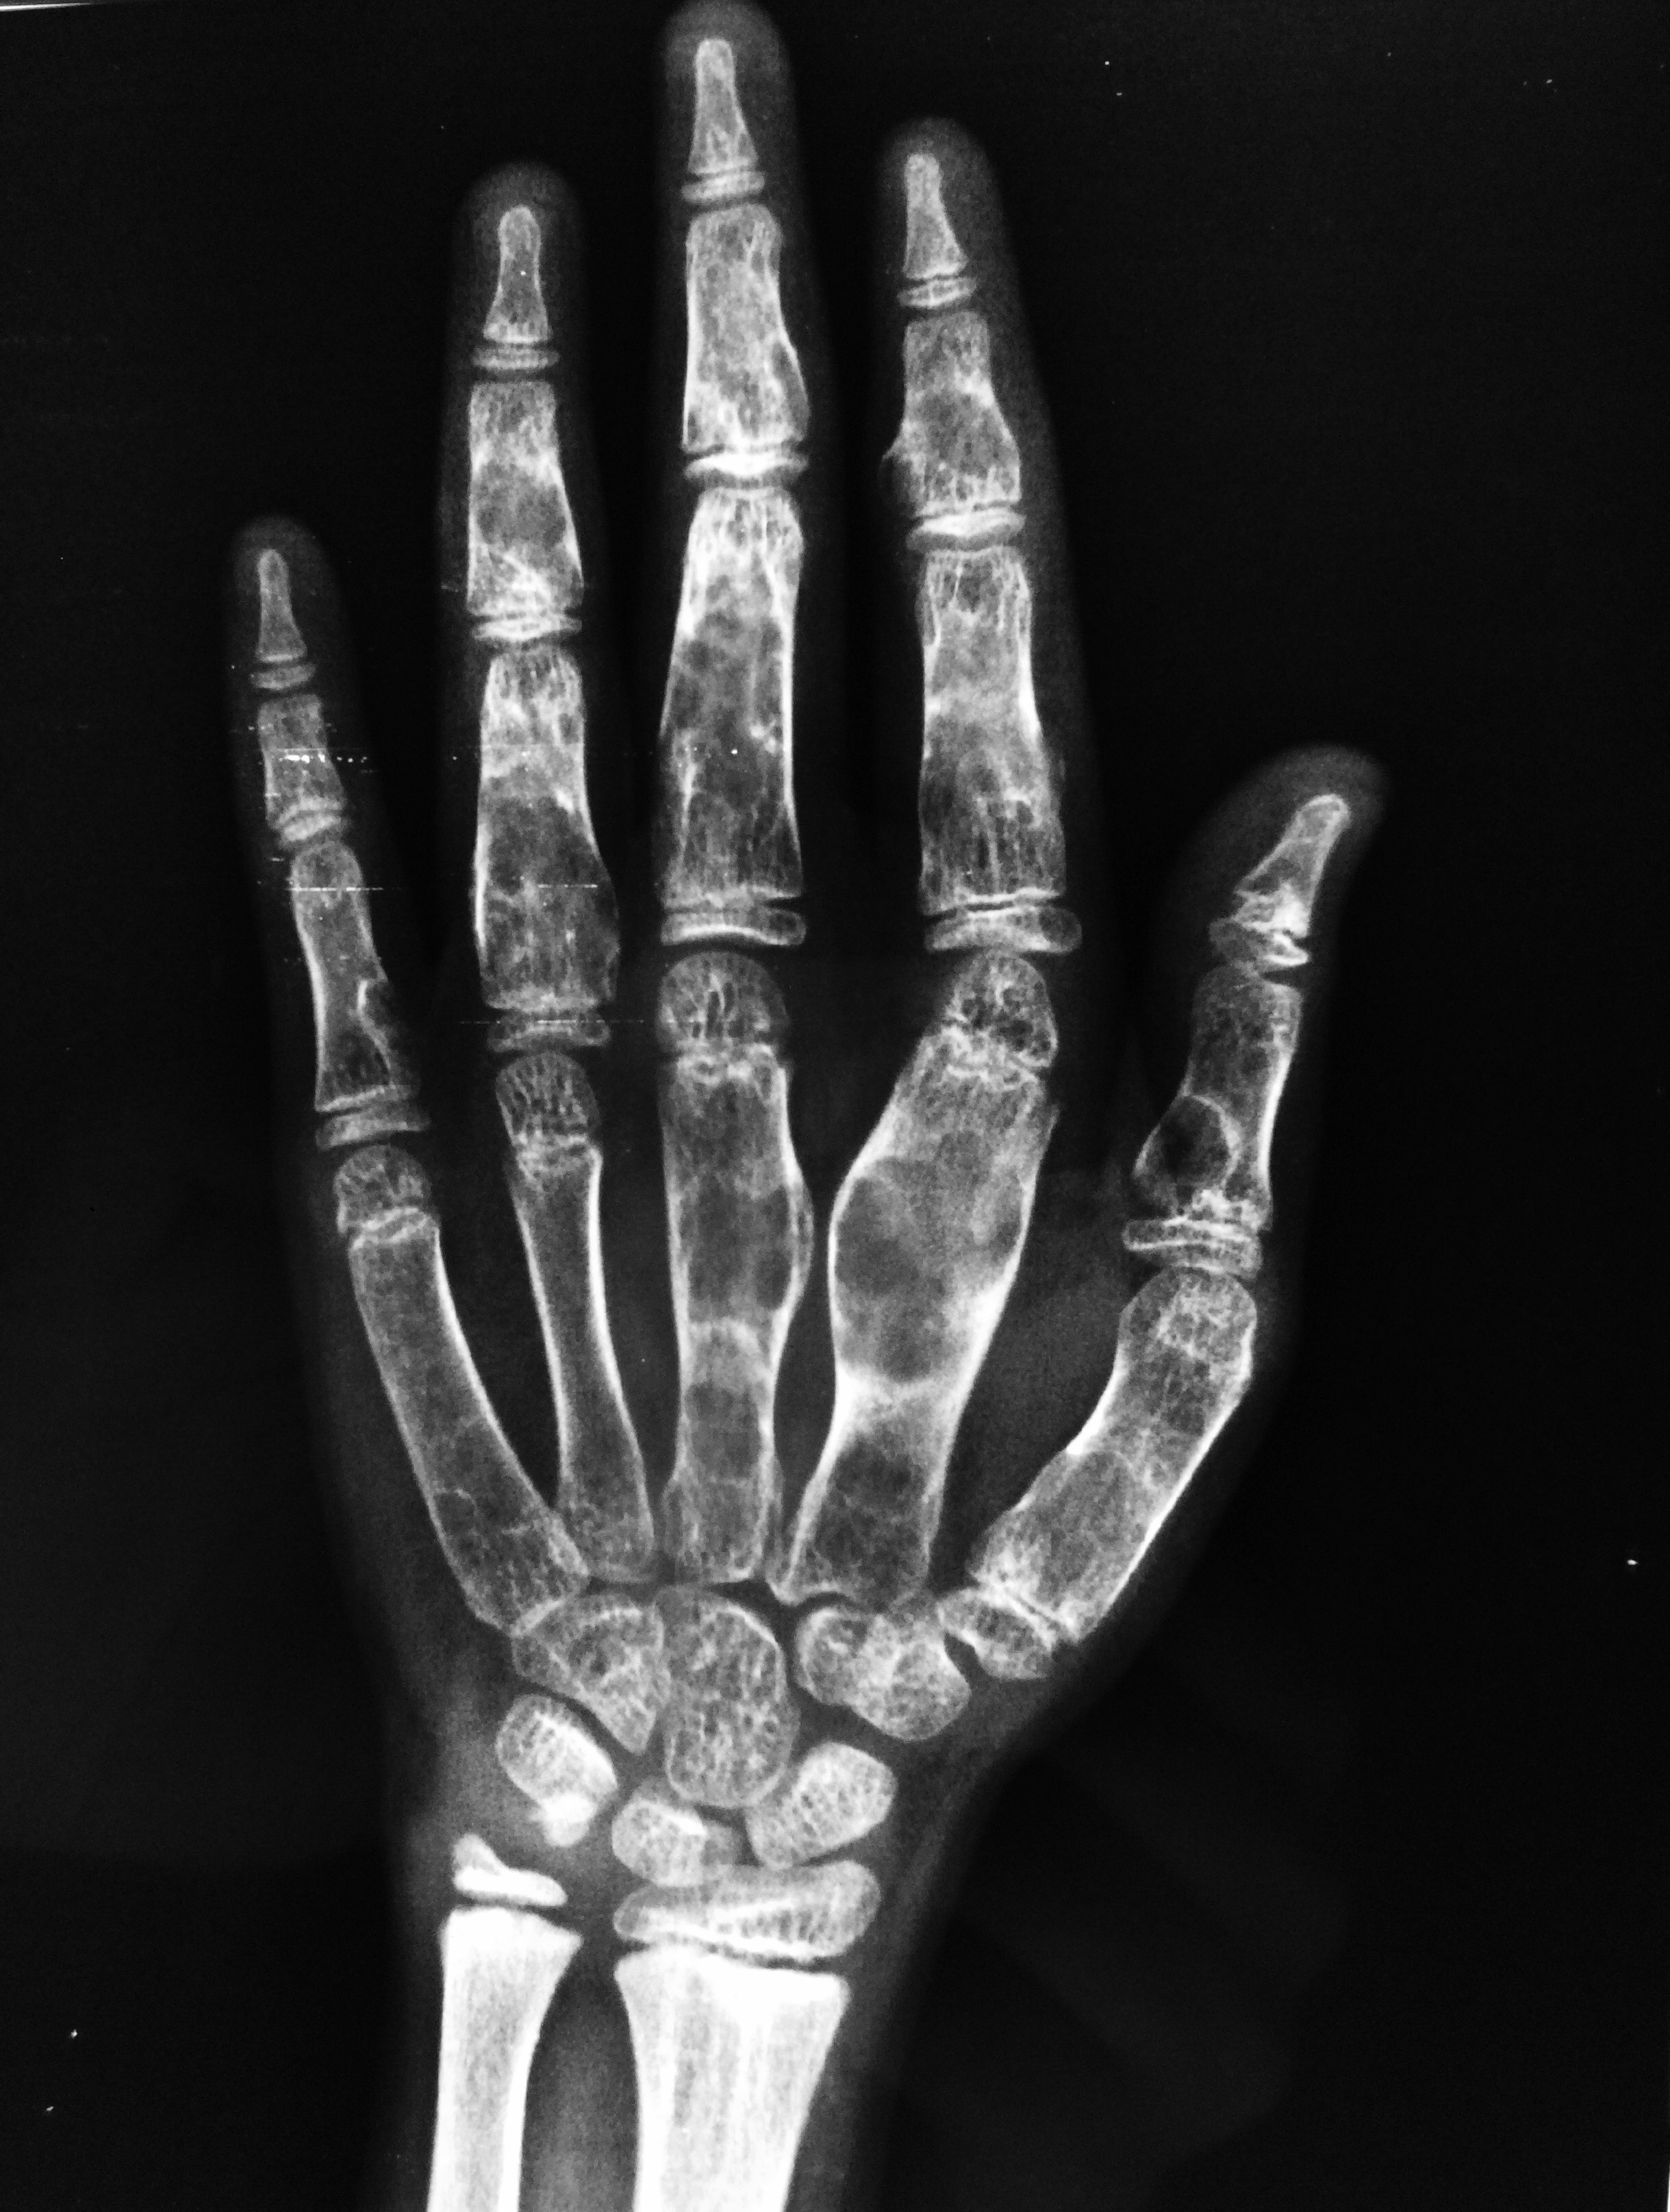

Welche Befunde erheben Sie auf dem vorliegenden Röntgen und MRT der Hand (T2fs und T1)? Verdachtsdiagnosen?